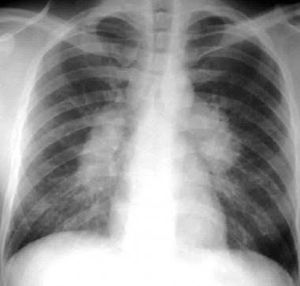

DDx? For this x-ray and most common cause

Bilateral hilar lymphadinopathy

There is hilar lymphadenopathy

Sarcoidosis is the most common cause

Hilar lymphadenopathy so most probably sarcoidosis